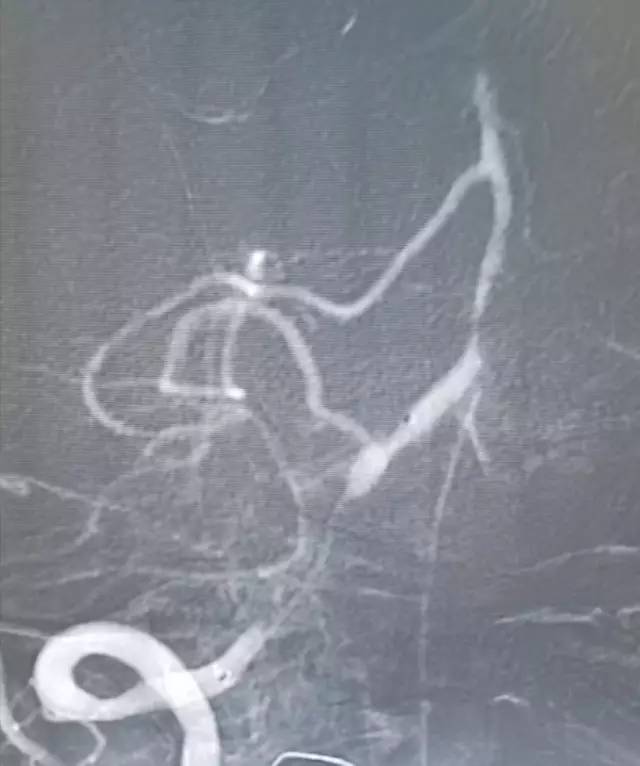

DSA:右侧椎动脉V4段重度狭窄,前向血流减慢,基底动脉近中段未见顺行显影,左侧椎动脉V4段远心端闭塞,右后交通动脉开放,经右颈内动脉造影可见基底动脉中远段显影,左胚胎型大脑后动脉(图3-5)。

图3

图4

图5

全麻下右股动脉穿刺置入6F动脉鞘,将6F导引导管至右椎动脉V1段,造影:右椎动脉V2段近段及远段狭窄。右椎动脉V4闭塞,右椎动脉V4远段经由脊髓前动脉代偿显影,左椎动脉由对侧椎动脉肌支及脊髓前代偿部分显影(图8)。

图8